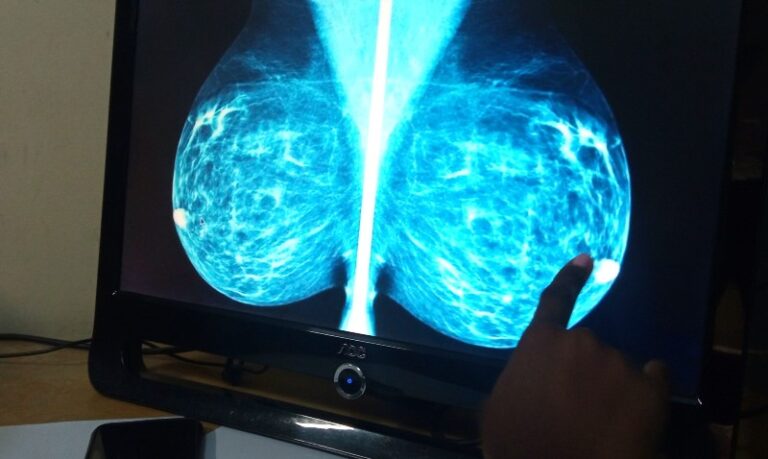

La mamografía es una herramienta esencial para la detección temprana del cáncer de mama, un tipo de cáncer que afecta a millones de mujeres en los Estados Unidos cada año. La detección temprana puede aumentar significativamente las posibilidades de supervivencia y tratamiento exitoso. Sin embargo, el costo de una mamografía puede ser una preocupación para muchas mujeres, especialmente considerando que los precios pueden variar considerablemente según la ubicación, el centro médico, el tipo de mamografía y la cobertura del seguro.

Existen diferentes tipos de mamografías disponibles, cada una con su propio costo. Las mamografías digitales, que utilizan tecnología avanzada para crear imágenes digitales, suelen ser más caras que las mamografías tradicionales de película.

• Mamografía digital: Este tipo de mamografía utiliza un sensor digital para capturar las imágenes, lo que permite una mejor visualización y análisis. El costo de una mamografía digital puede variar de $100 a $400 o más, dependiendo de los factores mencionados anteriormente.

• Mamografía 3D: También conocida como tomosíntesis, este tipo de mamografía toma imágenes del tejido mamario en múltiples ángulos, lo que proporciona una imagen tridimensional más detallada. Las mamografías 3D pueden ser más costosas, llegando a $400 o más.

• Mamografía tradicional: Este tipo de mamografía utiliza película para capturar las imágenes. Aunque es una opción más económica, las mamografías tradicionales pueden ser menos precisas que las mamografías digitales o 3D.